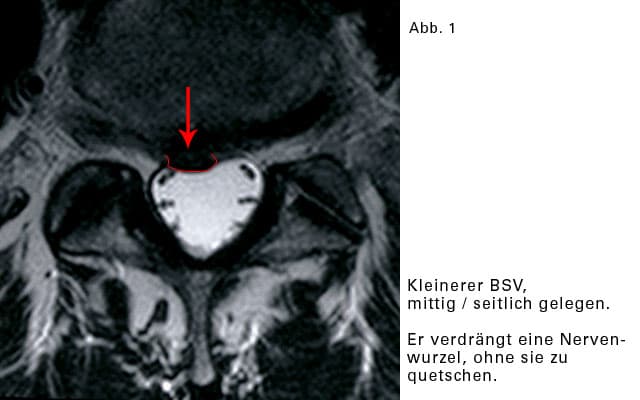

Seitlicher BSV:

Der Riss des Faserringes liegt seitlich, rechts oder links. Der Vorfall rutscht in den seitlichen Teil, und zwar in den knöchernen Austrittkanal eines Nerven. Hier ist relativ wenig Raum, und eine Quetschung der Nervenwurzel eher wahrscheinlich.